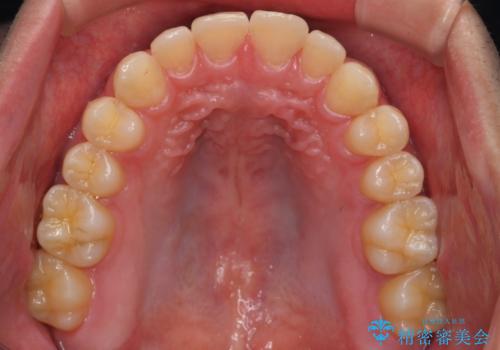

右下に乳歯が残っていましたが、後に続く永久歯がありませんでした。

乳歯も根が吸収しており長くは持たない状況でしたので、まず乳歯を抜歯し、他の歯を矯正治療で歯を並べてからインプラントで補綴しました。

先にインプラントをしてしまうと、矯正治療で周りの歯を動かす事ができなくなってしまいます。

矯正治療→インプラントの順で行います。